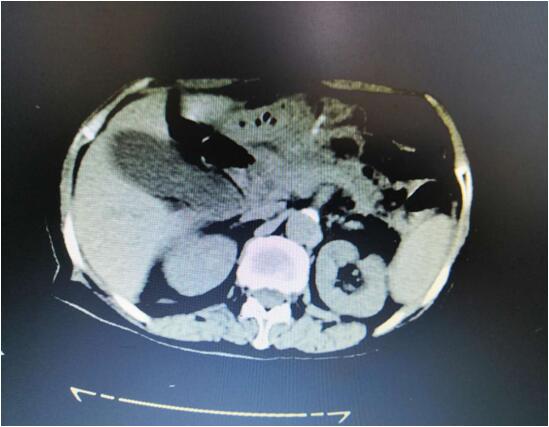

患者B,女,51歲,因牙齦出血1年入院,入院診斷為:乙肝,肝炎后肝硬化,門脈高壓癥,巨脾,脾亢,白細(xì)胞、血小板減少,中度貧血。5年前,曾在外院行介入脾栓塞術(shù),脾臟不僅沒有縮小,反而越來越大,脾下緣已經(jīng)超過腹部正中線、抵達(dá)臍部,就像幾個(gè)月“身孕”的婦女,給病人帶來巨大身心負(fù)擔(dān)。

(術(shù)前腹部CT顯示巨脾)